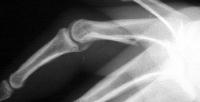

Palmar displacement of a portion of one condyle is visible on the lateral view.